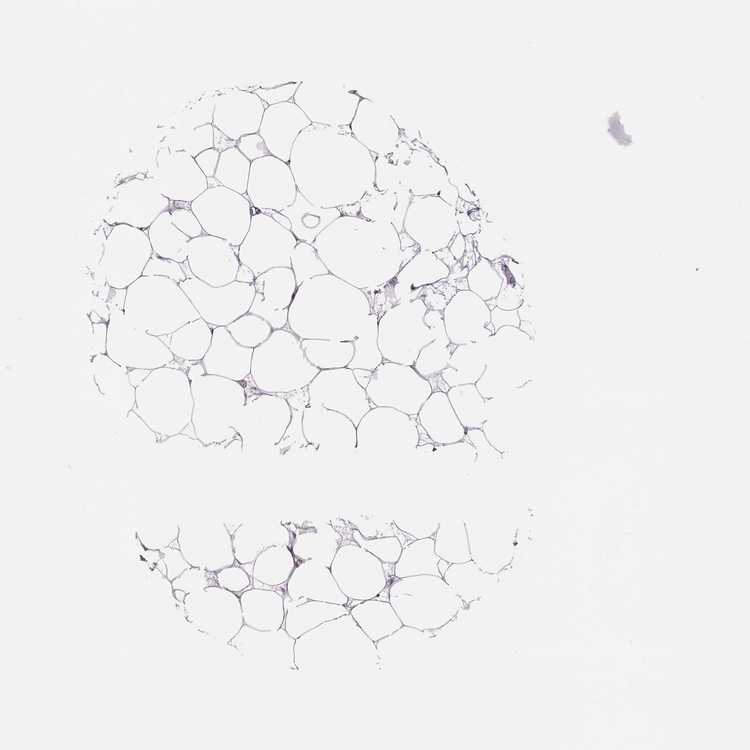

BREAST - Antibody stainingi

Antibody staining in the annotated cell types in the current human tissue is reported as not detected, low, medium, or high, based on conventional immunohistochemistry profiling in selected tissues. This score is based on the combination of the staining intensity and fraction of stained cells.

Each image is clickable and will lead to virtual microscopy that enables deeper exploration of all samples and also displays staining intensity scores, fraction scores and subcellular localization as well as patient and tissue information for each sample.

Antibody HPA072947

Adipocytes Not detected

Glandular cells Not detected

Myoepithelial cells Not detected